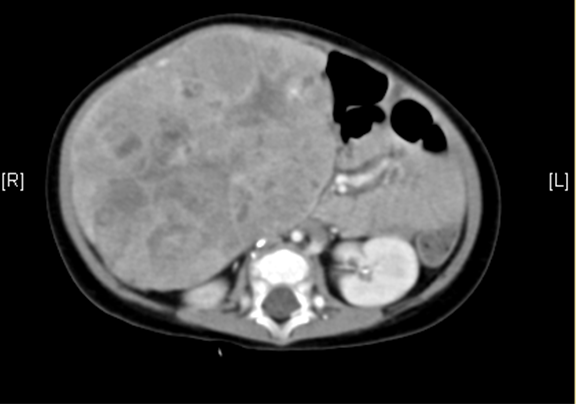

静脉期

辅助检查: 下腹部增强CT示:考虑肝母细胞瘤可能性大。

查体:腹部膨隆,腹壁静脉未见迂曲扩张,未见胃肠型及蠕动波。腹软,腹部触及一巨大肿物,至右髂窝,约20×15cm大小,质硬,边界不清,活动度差,无压痛、反跳痛,肝脾肋下未及。移动浊音(-),肠鸣音4次/分。